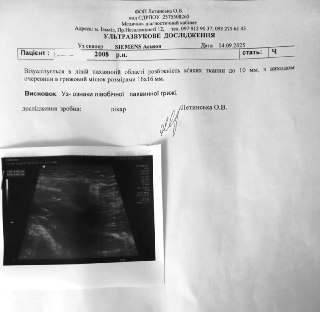

Друзі, сталася дуже неприємна ситуація, вже вдруге в мого брата виявили грижу, на цей раз лівобічну, і потрібна операція...